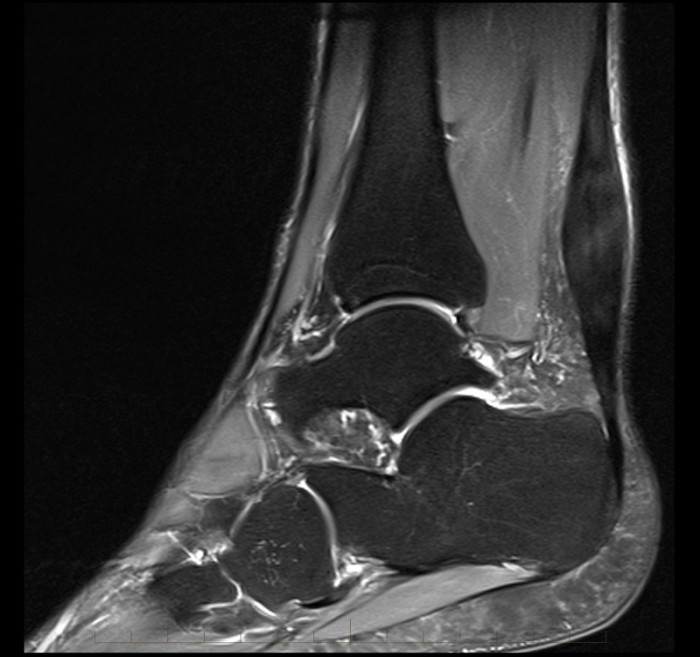

melbournemrileftachillestendonpartialthicknesstear5 MRI at What Is A Partial Thickness Tear Of A Tendon That means that the tendon is still attached to the bone, although it will be weakened. It’s usually described in terms of how deep the tear is in the tendon and doesn’t refer. Tendinosis occurs as we age. The primary cause of rotator cuff tears is a process we refer to as degenerative rotator cuff tendinosis. A partial rotator cuff. What Is A Partial Thickness Tear Of A Tendon.